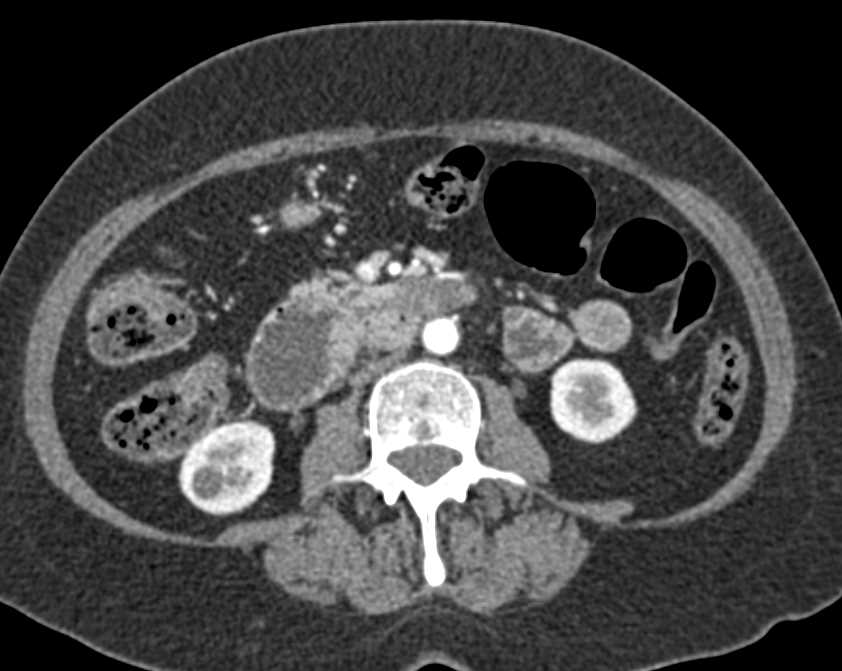

Duodenal Carcinoma with Obstruction